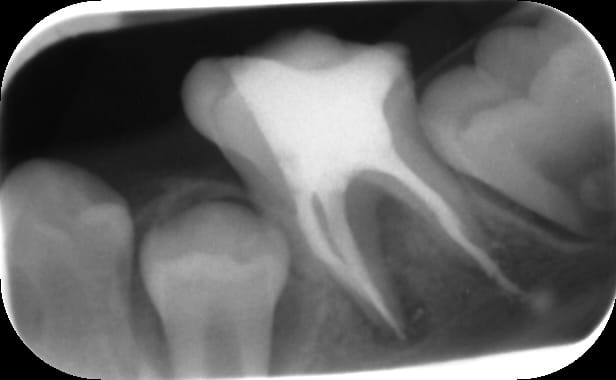

Je fais donc le parage: sous digue, avec hypochlorite , système de préparation Hero Shaper, radio cône calibré en place ok.

J'obture au Mac Spadden et je fais la radio post op: dépassement sur le canal distal, jusqu'au nerf alvéolaire inf !

Voici des radios:

Post op 1 qinen3 - Eugenol

Post op2 hvhcb9 - Eugenol

Apex pas assez fermé,pas d'obturation définitive.

Par ailleurs il faut se méfier des rx en 2D il n'est absolument pas sur que ce soit dans le même plan que le N.A.I.

C'est pas sûre qu'il n'y ait qu'un dépassement de pâte, ton cône de gutta est certainement aussi passé au delà de l'apex...

Un bon dépassement de pâte dans le canal NAI, ça m'est arrivé une fois, mais on voyait carrément une migration à l'horizontale du ciment canalaire, et paresthésie, ce que tu n'as pas.

En effet j'avais déjà vu des dépassement dans le NAI et il y avait ce déplacement horizontal de pâte.

Au risque de dire moi aussi une ânerie, je pense que tu es loin du canal. Si la pate part dans le canal, elle s'étend horizontalement comme l'a dit Piccalilly.

Les douleurs neuropathiques d'origines traumatiques peuvent survenir dans un délai libre. C'est dire dans la semaine (le plus souvent) ou dans six mois (plus rare). Vu la radio, le NAI ne semble pas touché (souvent le ciment tapisse le canal ce qui donne cette image de trait horizontal). De plus, les symptômes décrits évoquent une douleur de type inflammatoire tout à fait banale après un traitement endo. D'ailleurs le fait que les antalgiques usuels calme cette douleur va dans ce sens car les douleurs neuro ne cèdent pas avec les antalgiques de niveau I. Et pour finir, si lésion nerveuse il y a, la symptomatologie sera principalement de type déficit nerveux (hypoesthésie, anesthésie de la région mentonnière).